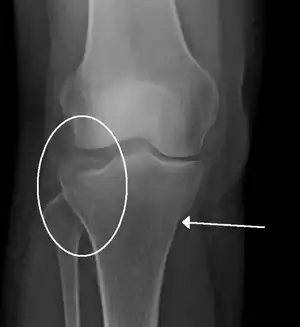

Subtle tibial plateau fracture on an AP X ray of the knee

A tibial plateau fracture seen on X-ray